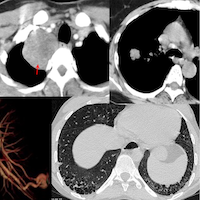

70-years old with a fibrosing ILD that shows a usual interstitial pneumonia (UIP) - like pattern on the left, but a three-density sign on the right suggesting this could be a bronchiolocentric interstitial pneumonia (BIP) pattern, suggestive of fibrotic hypersensitivity pneumonitis, if there is no underlying etiology (Fig. 1).